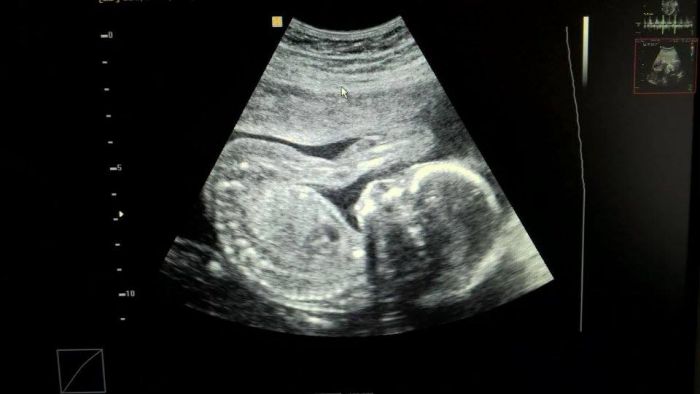

Čekáme na 10000 % dva kluky jako buky

Šlo to vidět, jak svina, ty jejich veliké pindoury

Jinak každý má cca 24 cm, to nevím jestli ze vším všudy... asi jo....

a váží přes 250 g + - vše je orientační, měřil to tak HALA BALA mi přišlo

Ted budou prý už více kynout, a příbírat a do délky budou růst pomaleji.....

Jinak včera jsme odpovídali podle MS, vše je jak má být, SRDÍČKA mají v pořádku, kosti a tělíčka taky, lodové vody OK, placenty pořád na přední stěně - pohyby PRÝ NEJDŘÍVE ZA 14 DNÍÍÍÍÍÍÍÍ

Fotečku mám jednu, zbytek se nepovedl, a mám prý více JÍST...........Že prý at si uvedomím, že to co s ním, si dělí dvě mimina a ne jedno..... a že + 5 kg je málo (že mám mít už + 10 kg) JE TEN DOKTOR V POŘÁDKU?